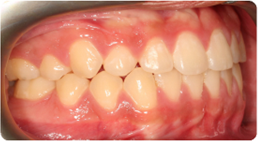

Each case shows the front view and an arch or side view, before and after BioLign Method-guided treatment.

Protruding front teeth aligned and brought into ideal occlusion